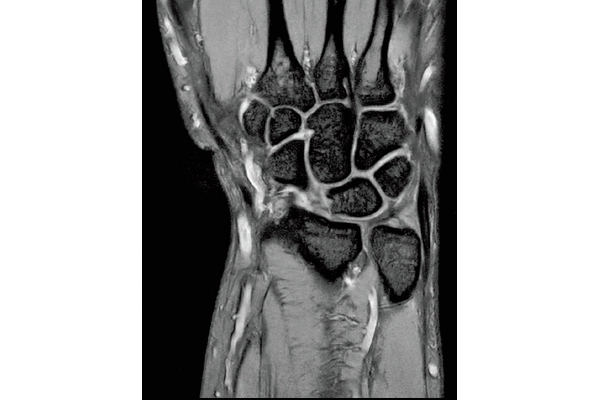

3D Bone

0.93×0.93×1.2(0.6)mm

1.1×1.1×1.2(0.6)mm